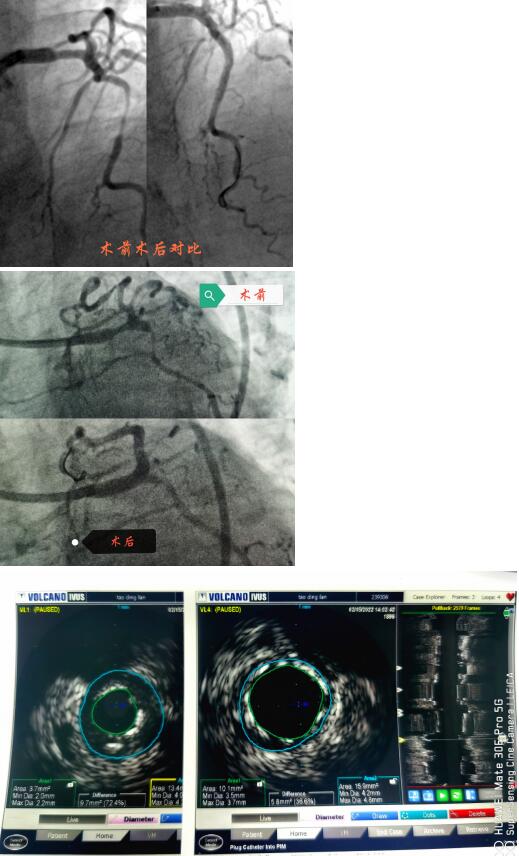

春節(jié)剛過,陶奶奶的孩子們帶著陶奶奶再次來到了江寧中醫(yī)院心內(nèi)科準(zhǔn)備拆除這顆潛在的“致命炸彈”。韋鋒主任反復(fù)研究陶奶奶的前期手術(shù)影像,心中擬定著多個(gè)手術(shù)方案。經(jīng)過充分準(zhǔn)備,2月15日,韋鋒主任再次為陶奶奶進(jìn)行了介入手術(shù)。術(shù)中通過血管內(nèi)超聲(IVUS)精細(xì)、準(zhǔn)確評估陶奶奶的冠脈病變情況,發(fā)現(xiàn)陶奶奶的左主干最小管腔面積僅僅3.7mm2,;前降支近段全程鈣化,最嚴(yán)重處呈270度的環(huán)形鈣化,最小管腔面積僅僅2.1mm2;回旋支開口正常,回旋支近端最小管腔面積1.8mm2。韋鋒主任根據(jù)IVUS的結(jié)果,改變了原來擬定的DKCRUSH術(shù)式,決定采用藥物球囊和藥物涂層支架相結(jié)合的方式處理病變(LCX藥物球囊,LM-LAD植入支架),經(jīng)過近2個(gè)小時(shí)的手術(shù),陶奶奶的冠脈血管又“完美”地回來了。

韋鋒主任術(shù)中在仔細(xì)研究陶奶奶的IVUS結(jié)果,指導(dǎo)手術(shù)更精確的進(jìn)行。